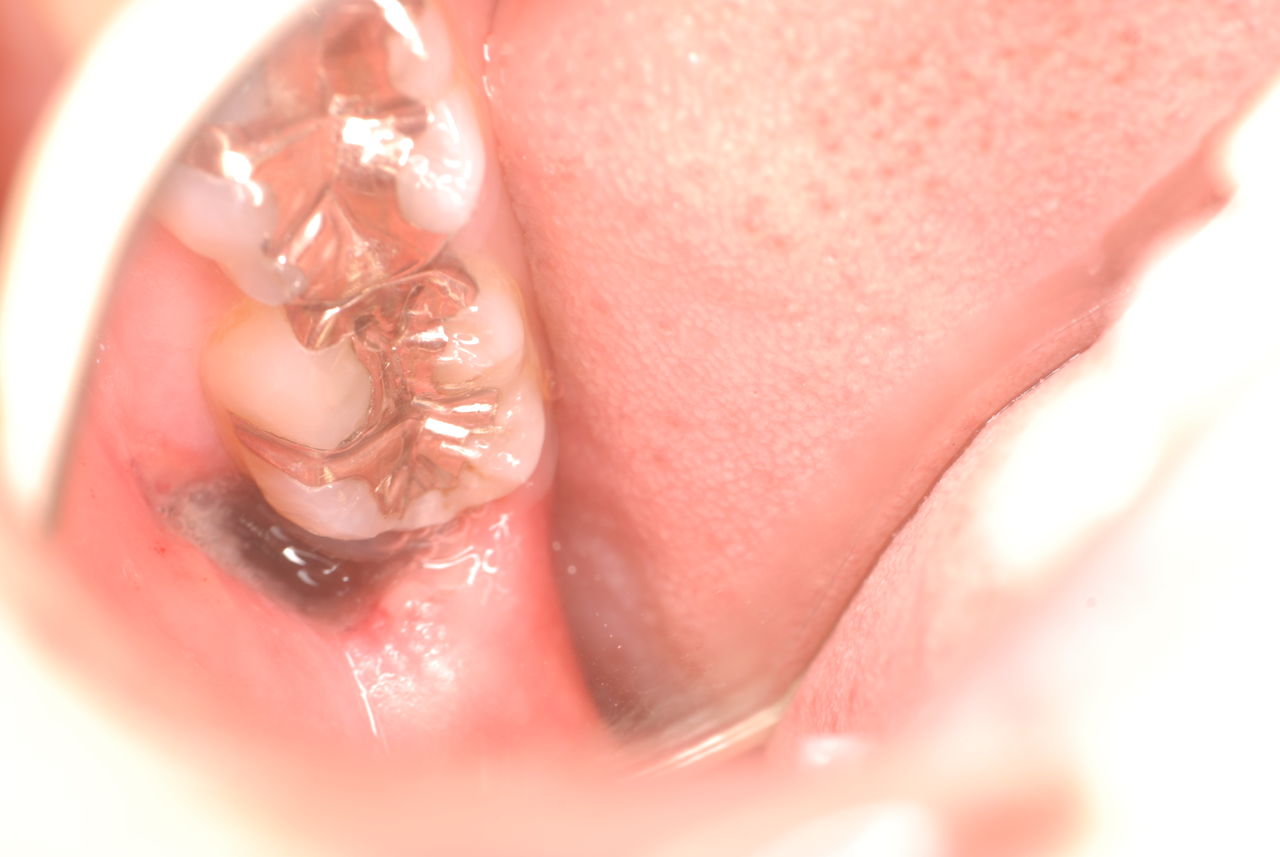

左下の歯は歯の中の治療も?ですごい歯周病を患い歯茎の穴(ポケットと呼ばれるところ)から膿が出ているのです。ばい菌と毒素で骨が溶けて深い穴ができてそこにまたバイキンと毒素がたまるという悪循環ができているのですね。

右下の歯は歯の中の治療もあやしいのですが、金属と歯の間がすでに虫歯で崩壊し始めています。

プラークというバイキンと毒素と食べかすの塊が歯の周りや歯茎にまとわりついて虫歯になり且つ重症の歯周病を患っています。